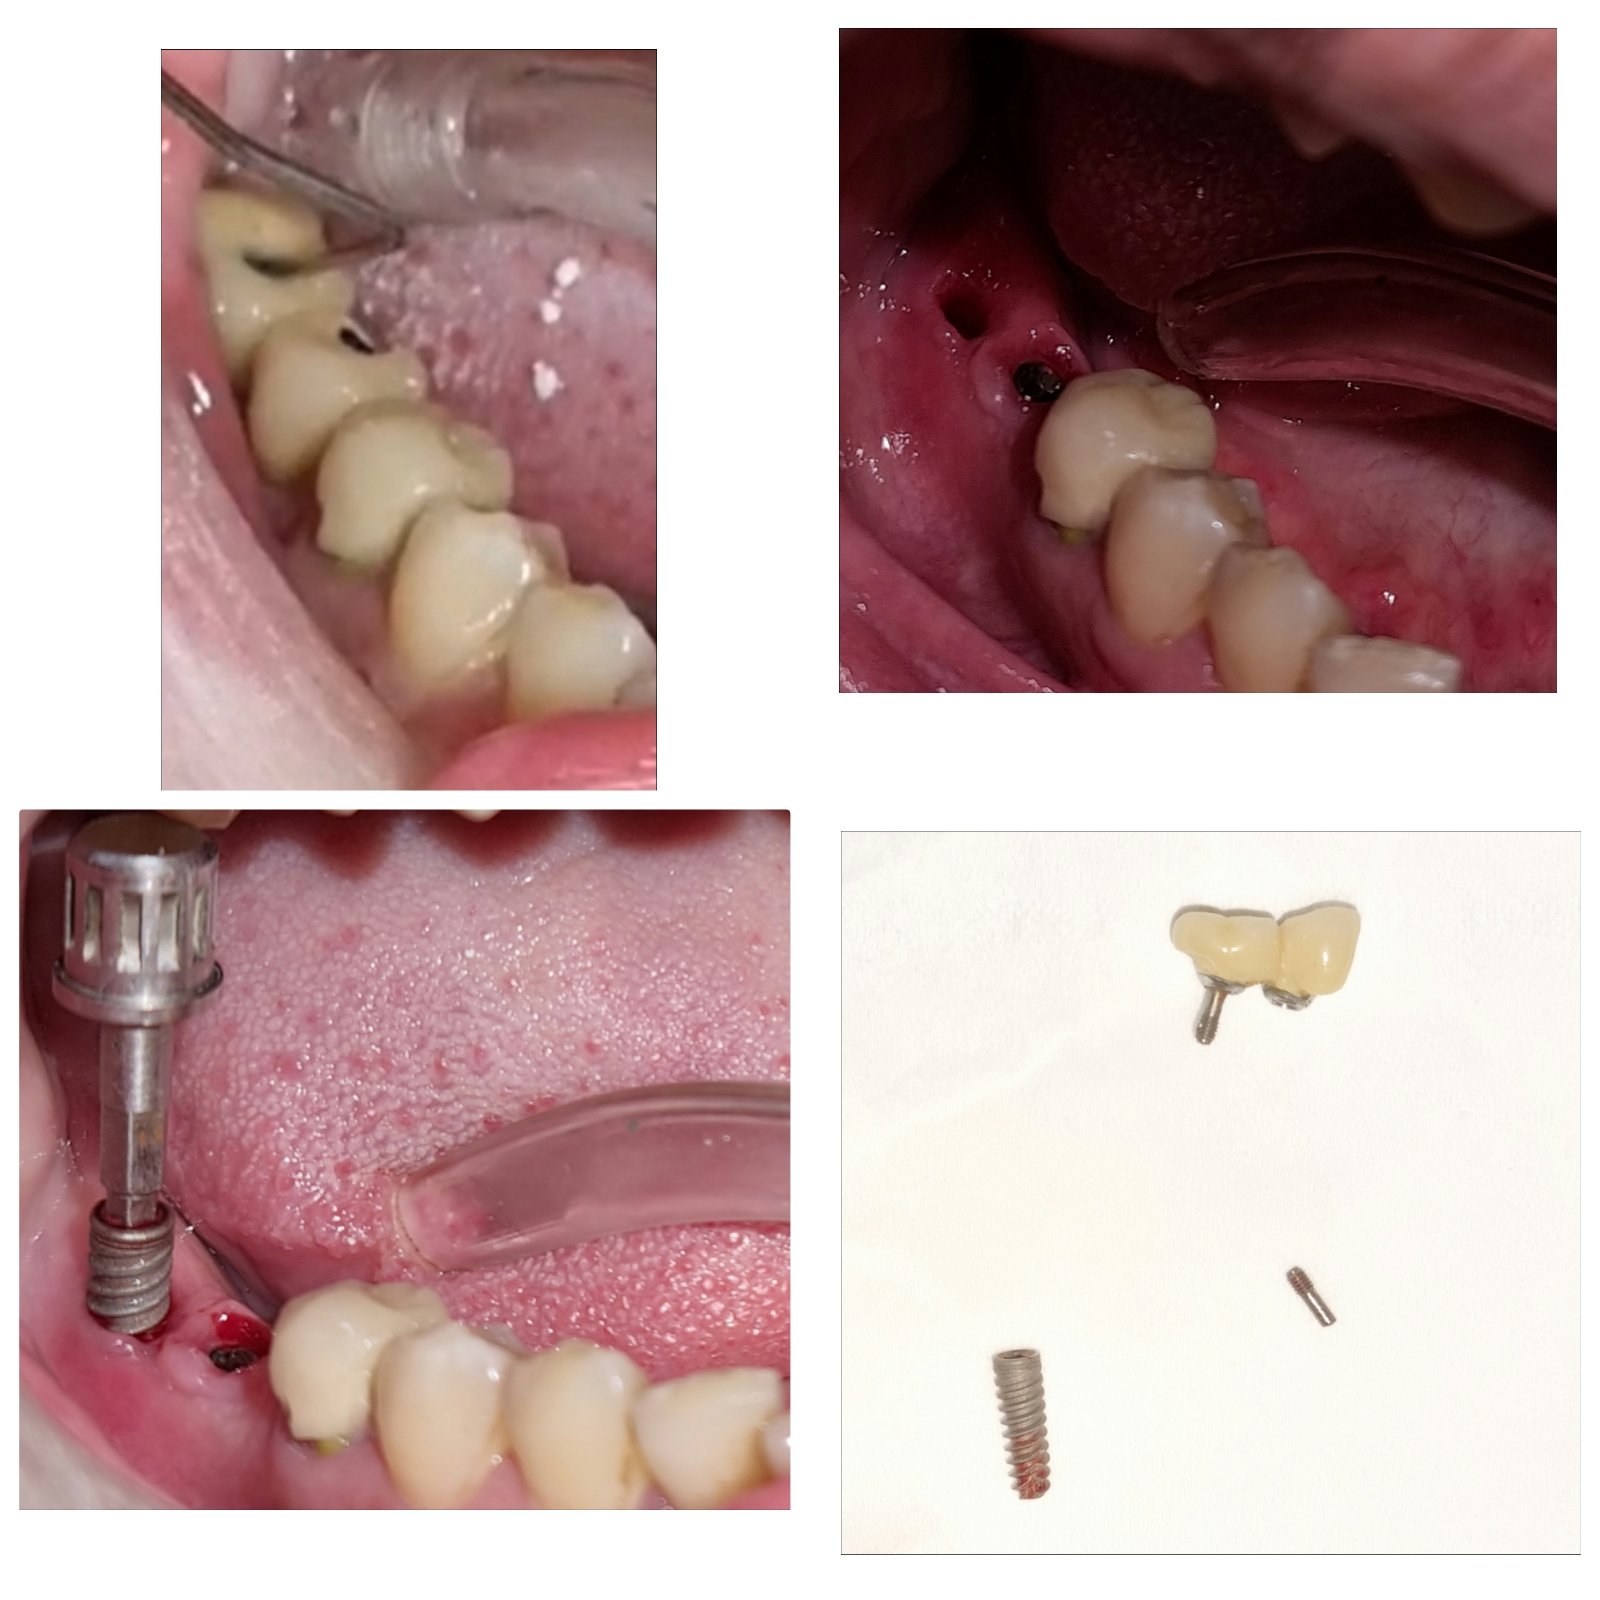

Dental implant surgery is a procedure that replaces tooth roots with metal, screwlike posts and replaces damaged or missing teeth with artificial teeth that look and function much like real ones.

Dental implant surgery can offer a welcome alternative to dentures or bridgework that doesn't fit well and can offer an option when a lack of natural teeth roots don't allow building denture or bridgework tooth replacements.How dental implant surgery is performed depends on the type of implant and the condition of your jawbone. Dental implant surgery may involve several procedures. The major benefit of implants is solid support for your new teeth — a process that requires the bone to heal tightly around the implant. Because this bone healing requires time, the process can take many months.

- Immediate